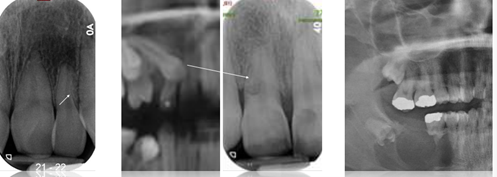

Persistent periapical radiolucency - apex nibbled away by chronic inflammation

restoration encroaching on pulp PA and resorption mesial root, trauma

PA radiolucency, apex nibbled away, incisor has bad endo inflammation grown to overlap canine

* need to remove inflammation source to solve (endo canine wont solve alone)

The pulp is necrotic - bacterial or dental trauma in origin

The periapical inflammatory lesion precipitates the resorption process

In actual fact the majority (81%) of teeth with periapical lesions will have microscope areas of root resorption

* Only 7% of these are detectable radiographically